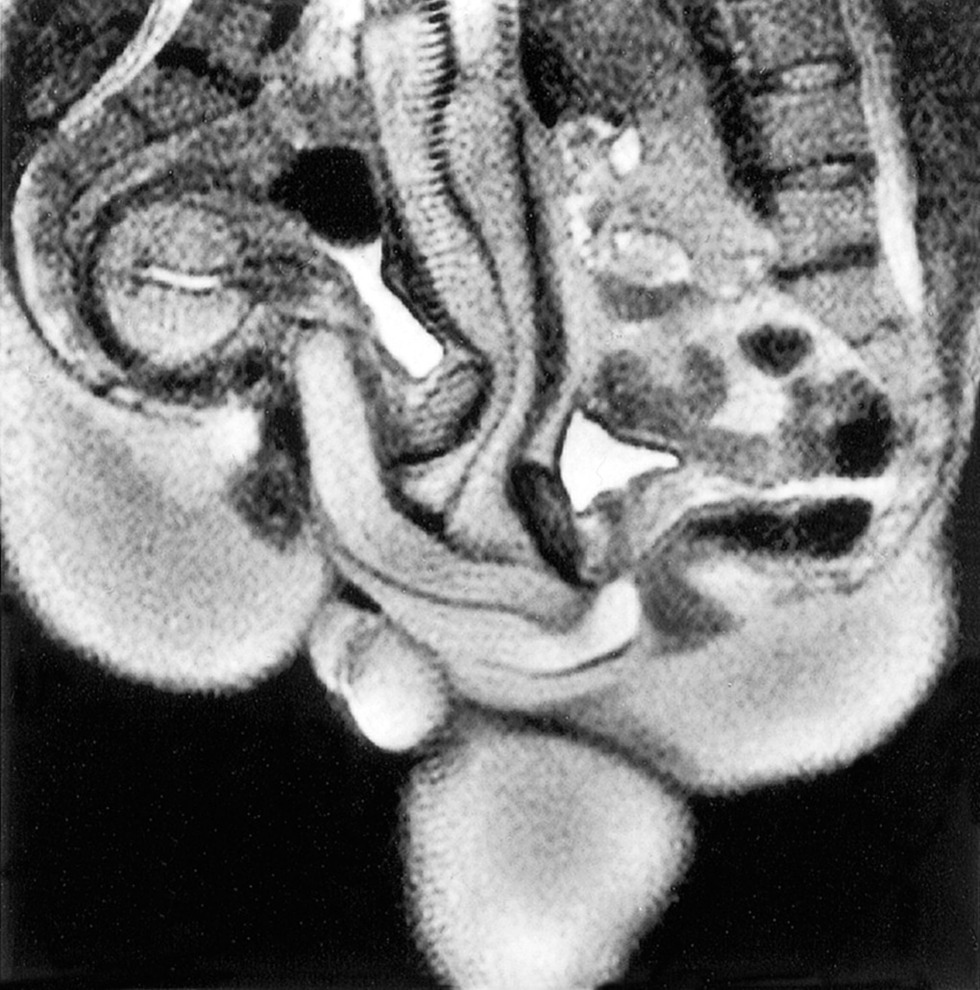

Penis in the vagina in the section

Intercourse in the section

Anatomy of sexual intercourse in the section